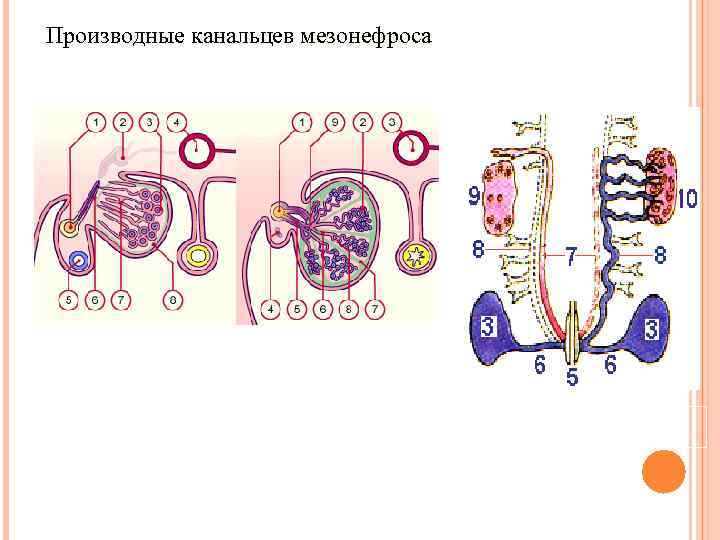

Производные канальцев мезонефроса

Производные канальцев мезонефроса